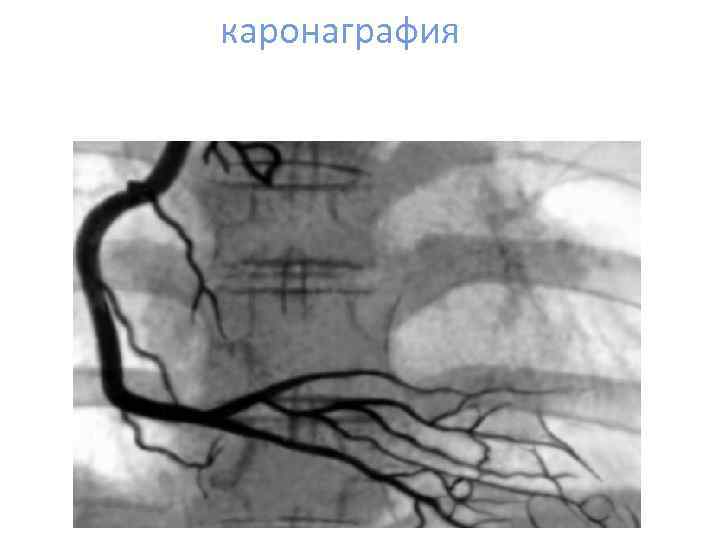

каронаграфия